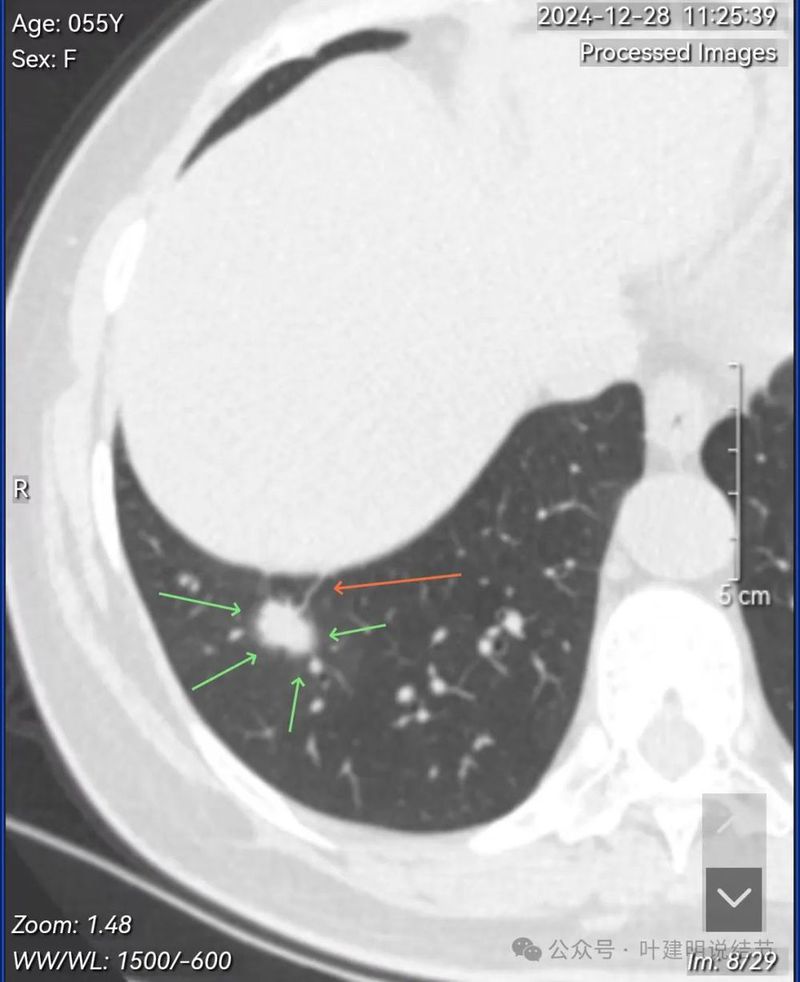

再看在我门诊时2025年1月14号复查的靶扫描影像:

血管进入与异常增粗并散开来(在肿瘤性病变中,这种表现是浸润性而且风险大的表现)。

血管进入穿行并异常增粗,磨玻璃成分显得较为散在,缺乏聚拢性。

右下这个病灶前后对比一看,范围已经有缩小,如果没有12月份的影像,假如靶扫描这次的是首次发现,那感觉更倾向恶性些,只是比如收缩力不明显、瘤肺边界有的层面欠清晰等不太符合,但总体上仍得高度怀疑恶性的可能性,至少不能掉以轻心。但由于有12月28日的影像在前,我们发现短短半个月左右的时间,病灶实性成分明显吸收,磨玻璃成分占比增加,显然不可能是恶性的,就是个炎性病灶处于开始吸收但还没有吸收完的状态。而若捌开靶扫描这次的影像只看前次平扫,那么反而更倾向良性的炎性的。最归关键的是:实性病灶边缘有圈“晕”征!实性病灶伴晕征的基本上不太可能是肿瘤性病变。而且此灶整体上看实性却缺乏收缩力,肿瘤不是这个样子。当然若是粘液性腺癌或小细胞癌或鳞癌,也可以缺乏收缩力,但小细胞癌或鳞癌的轮廓与边界要更清楚些。只有粘液腺癌倒也可能类似表现,这时候适当随访是区分鉴别的重要手段。